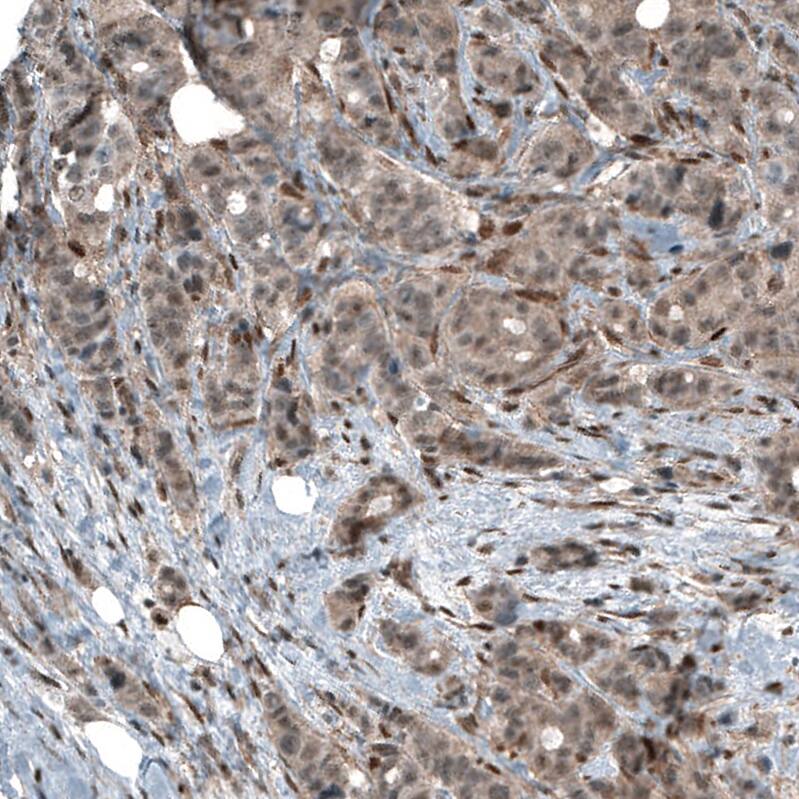

Staining of human breast cancer shows moderate cytoplasmic positivity.